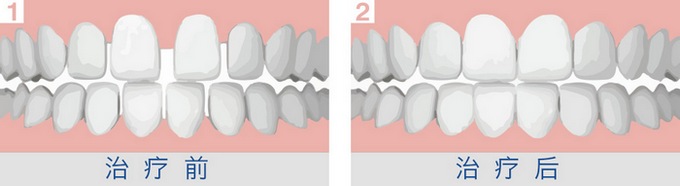

大连康贝佳口腔医生指出,牙列稀疏的危害大,家长要在孩子长牙开始之前就应该注意孩子的牙齿是否健康生长,如果发现有类似牙列稀疏等牙齿问题,要及时做好预防治疗的工作。那么,下面我们来看看怎么预防牙列稀疏。

1、孩子在2.5-6岁左右,口内一般是乳牙,在这一时期,如果患儿牙齿数目、形态、大小正常,同时颌骨发育正常,牙列中出现散在的间隙,看似牙列稀疏,然而这一般是正常的。此有利于恒牙的正常萌出,临床上一般毋需矫治。如果牙体态小,颌骨形态正常;口内先天缺牙,颌骨形态正常;牙体形态正常,颌骨过大等,其往往造成牙列稀疏,此为疾病的征象,需加以矫治。

2、从6岁至12岁左右,此年龄段内,口内乳恒牙同时存在,这一时期牙列稀疏不常见,临床上常见到的乳牙早脱或恒牙迟萌以及由于唇系带附离异常所致的牙间间隙,此一时期只要针对病因,对症矫治,常可收到较好矫治效果。

3、在乳牙全部替换掉、恒牙萌出后,由概述中所述及的四种类型所致的牙列稀疏,只要及早矫治,一定疗效较好,若错过12-16岁这一年龄后再行矫治,往往疗程较长、疗效不能肯定,此期可正颌手术治疗。

温馨提示:以上就是【预防牙列稀疏从娃娃抓起!】的相关介绍。牙列稀疏易于嵌塞食物而损伤牙周组织,引起牙龈炎,牙周炎,同时易于龋变。严重者可影响患者的容貌美观,造成心理精神障碍。此病及早根据引起牙列稀疏的原因,进行不同方法的矫治。还有相关口腔问题建议与我们的进行在线咨询。